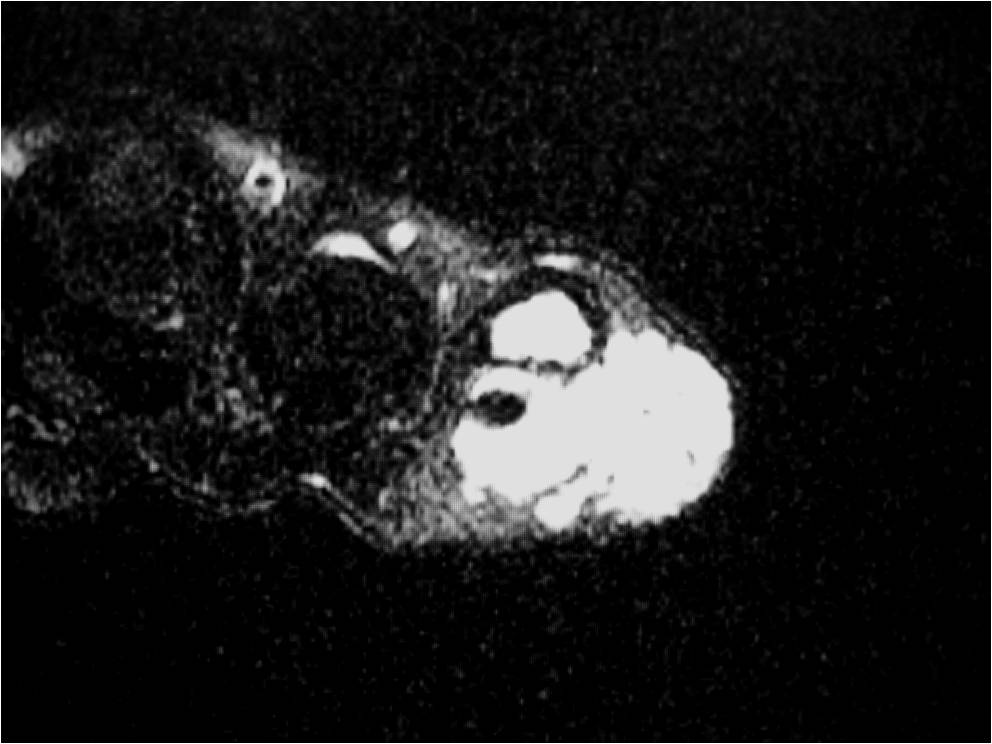

MRI

• Isointense to muscle T1

• Low to intermediate T2

• May bloom on gradient echo (hemosiderin deposition)

• May demonstrate intense enhancement

Fig. 2-5: MR images of the hand with a giant cell tumor of tendon sheath shows a mass isointense to muscle on T1W and intermediate to high signal on T2W images. The lesion does not infiltrate the bone.